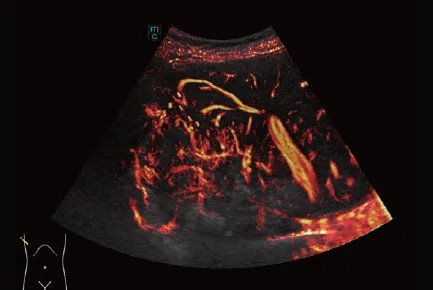

The m-Elite event featured numerous insightful academic presentations, with the live contrast-enhanced ultrasound (CEUS) demonstration co-conducted by Professor Jung and Dr. Becker stealing the spotlight. Using Resona A20, the team performed CEUS and fused the images with MRI scans, showcasing the technology’s ability to deliver ultra-high-definition contrast imaging with rapid 4-5 second response times and accurate lesion capture. The demonstration was live-streamed globally via the RayInsight Ecosystem’s remote ultrasound system.

Professor Clevert from the University Hospital Munich shared his research on High-Frame-Rate Contrast-Enhanced Ultrasound (HiFR CEUS): "HiFR CEUS allows doctors to easily visualize blood vessels and microbubbles, eliminating the need for interventional procedures in many cases. In our experience, the image quality of this ultrasound system is exceptional—even superior to CT or PET-CT."

"Today, using Resona A20’s micro-contrast imaging technology, we can detect liver tumors smaller than 5 millimeters," stated Professor Jung, Director of the Ultrasonic Medicine Center at the University Hospital Regensburg— a remark that resonated deeply at the m-Elite event.